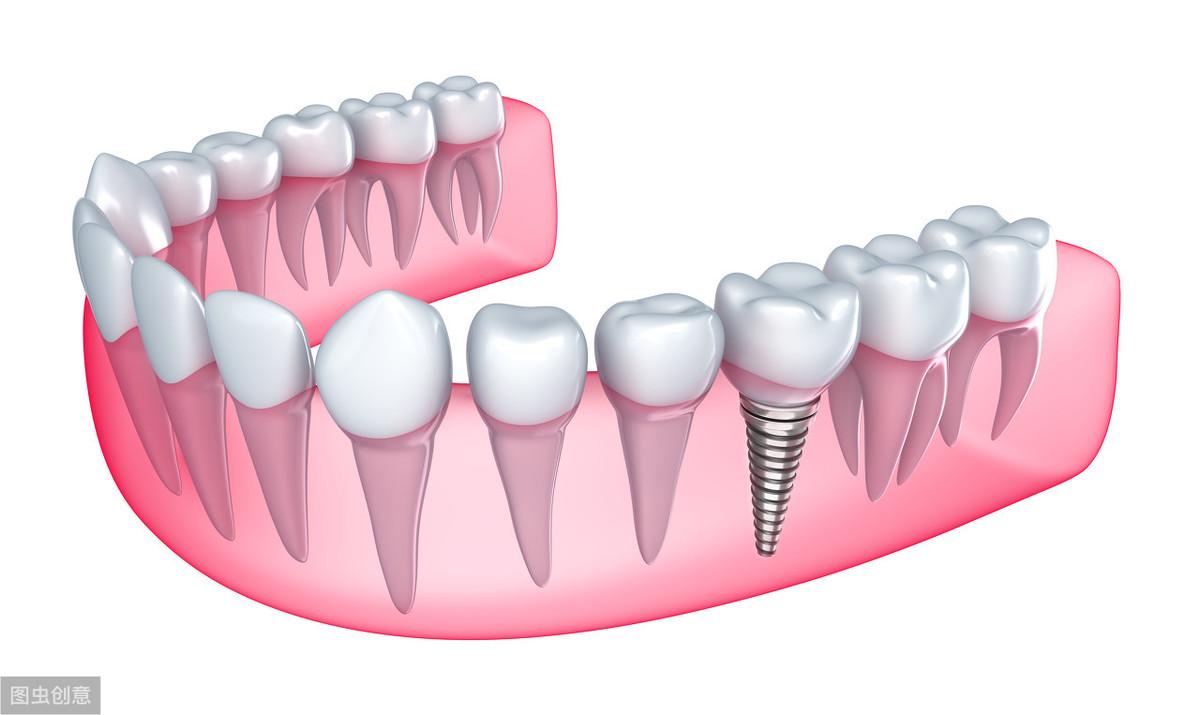

種植牙技術(shù)是近幾十年出現(xiàn)在大眾視野中的一種修復(fù)缺失牙體的方法。一顆完整的種植牙體由三部分組成:種植體、基臺(tái)、人工牙冠。

手術(shù)過(guò)程就是將種植體植入患者的牙體缺失處,待其傷口愈合,種植體與牙槽骨結(jié)合牢固后,將基臺(tái)安裝在種植體上,再將人工牙冠安裝在基臺(tái)上,形成完整而堅(jiān)固的人工牙體。

種植牙技術(shù)就像在缺失牙體處種一顆新的牙齒,能夠和牙槽骨結(jié)合,做種植牙能有預(yù)防牙槽骨萎縮,這是普通的假牙無(wú)法做到的,而且種植牙體不依附周圍鄰牙,對(duì)鄰牙不造成任何負(fù)擔(dān),所以相對(duì)其他修復(fù)手段,不僅更為牢固不易松動(dòng),且使用壽命長(zhǎng),果好。